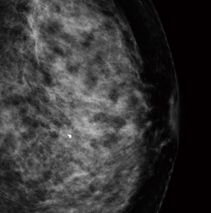

■症例2:dense breastの中のmass

症例2:2D画像(所見部分拡大) |

症例2:トモシンセシス静止画像 |

症例2:左CCの2D画像 |

症例2:左CCのトモシンセシス静止画像(11スライス目) |

症例2:左MLOの2D画像 |

症例2:左MLOのトモシンセシス静止画像(19スライス目) |